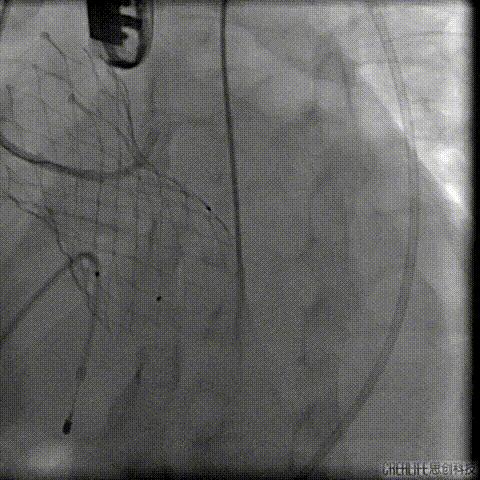

术后行急诊CT检查

TAVR术后3日Hb较前下降 (63g/L)

CT提示左侧腹膜后、髂窝及腹股沟区巨大血肿

行急诊手术 腹主动脉及左侧股动脉造影

左侧股动脉见造影剂外渗